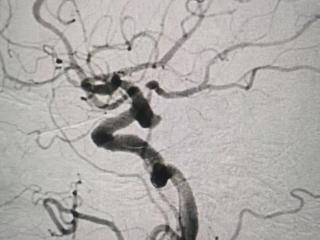

妙手“神龙摆尾”攻克手术难关——平度市第三人民医院成功为八旬老人完成高难度脑动脉瘤介入治疗